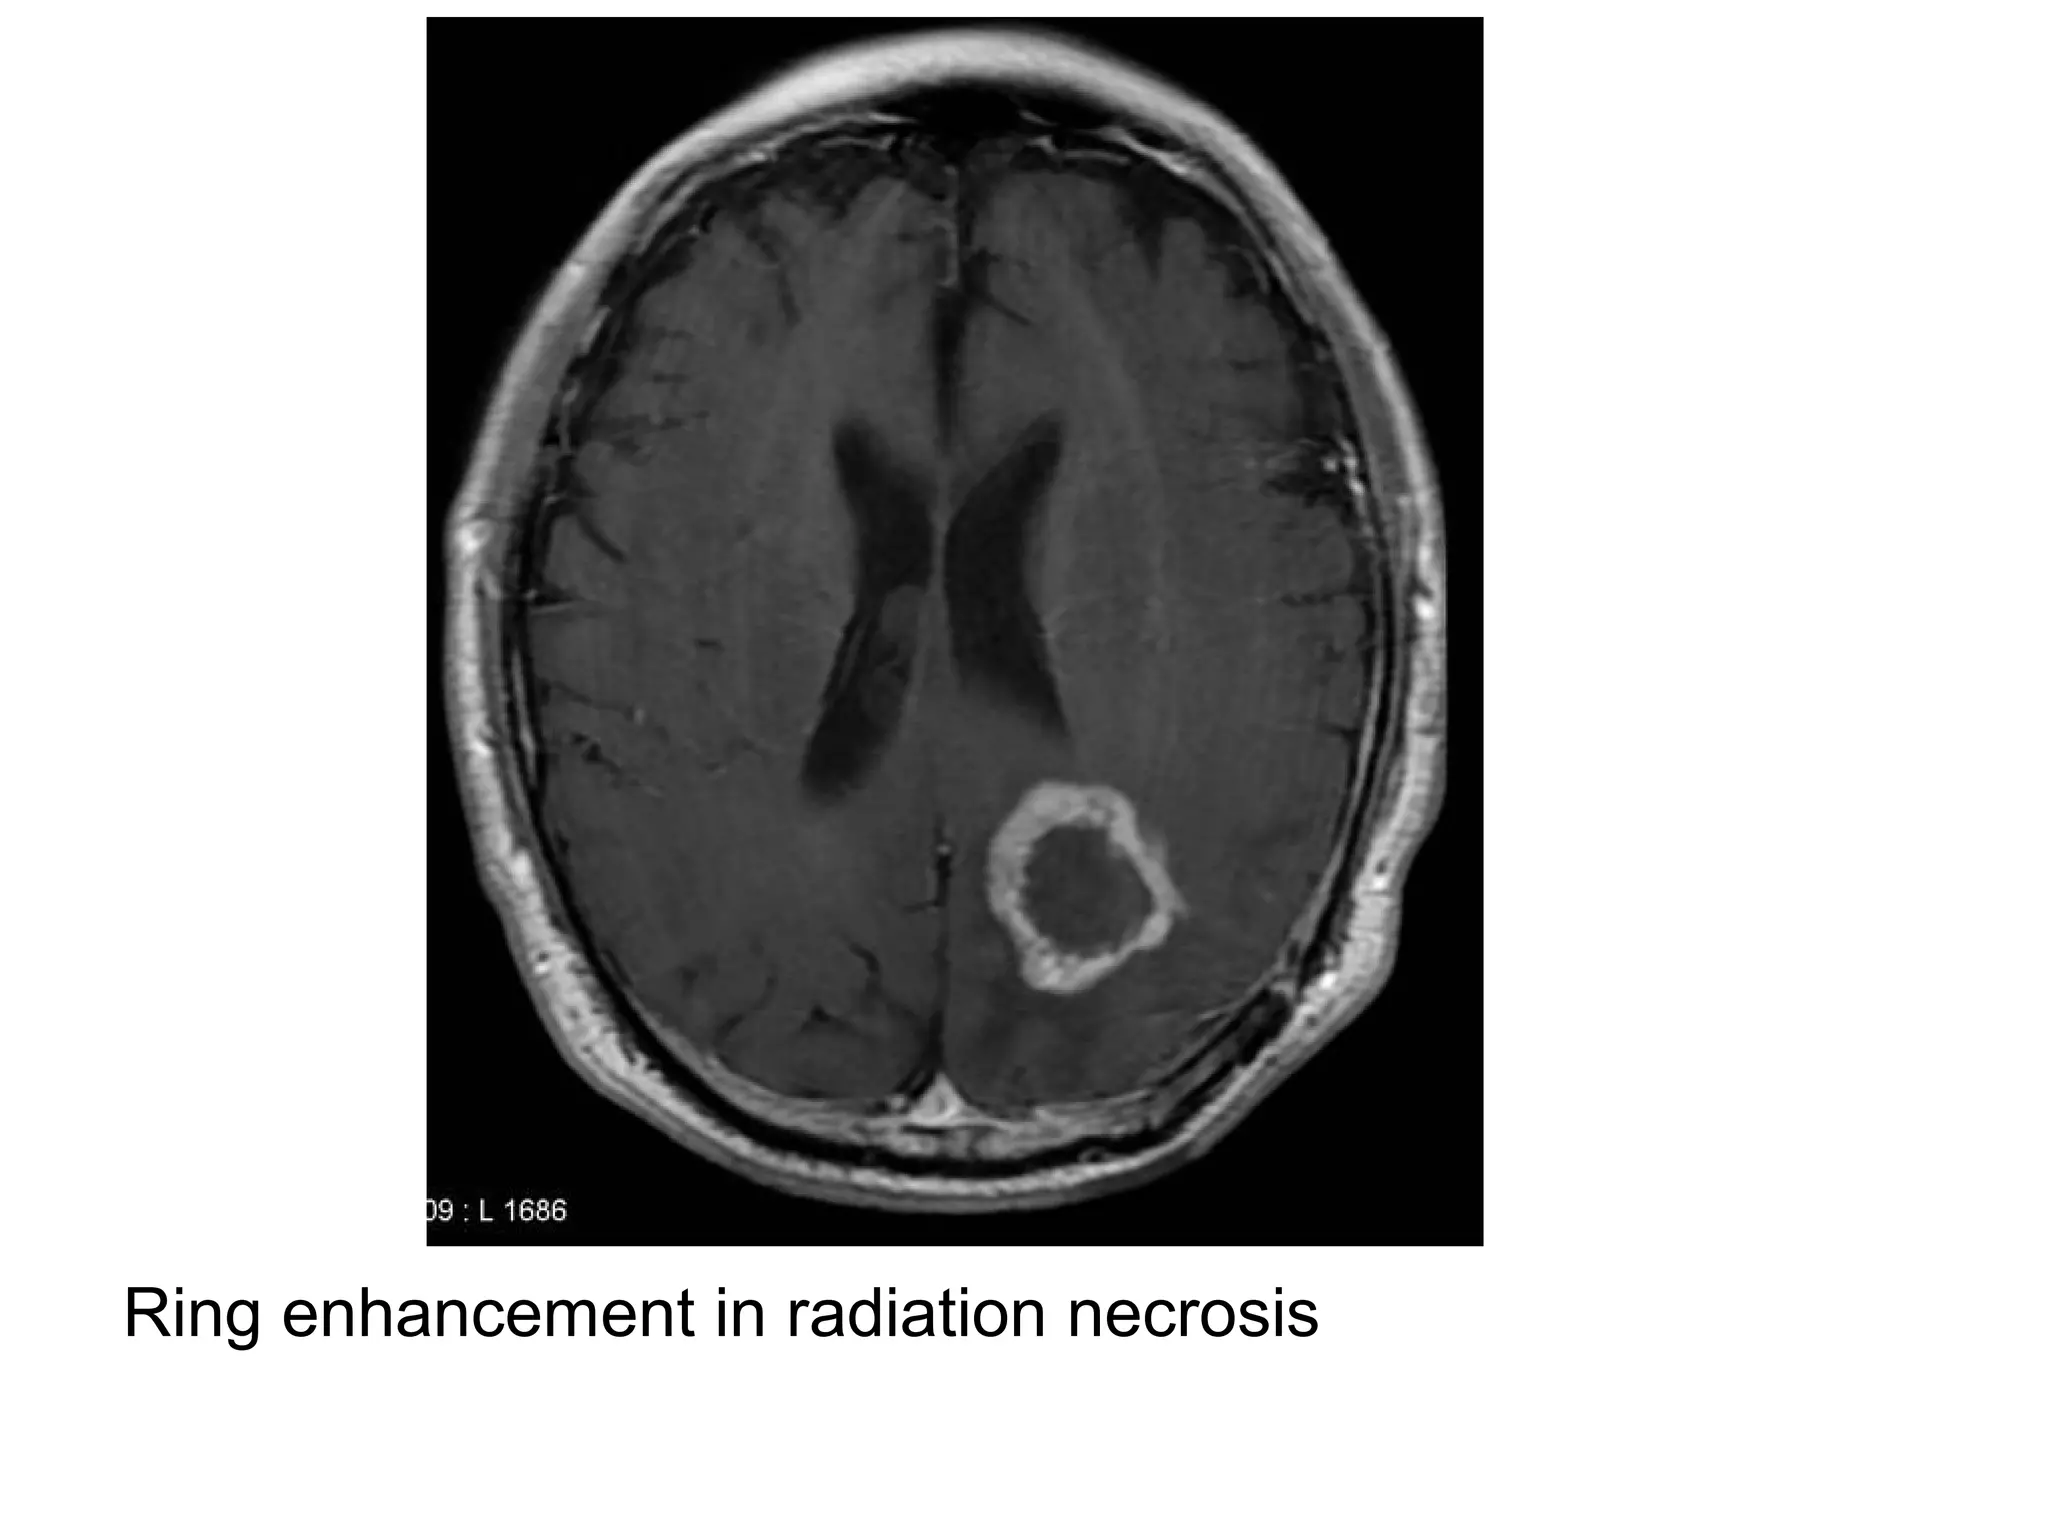

7-Radiation Necrosis (may look identical to

a high-grade tumor, on perfusion, cerebral

blood volume is generally low in radiation

necrosis and typically increased in a high

grade glioma)

Ring enhancement in radiation necrosis